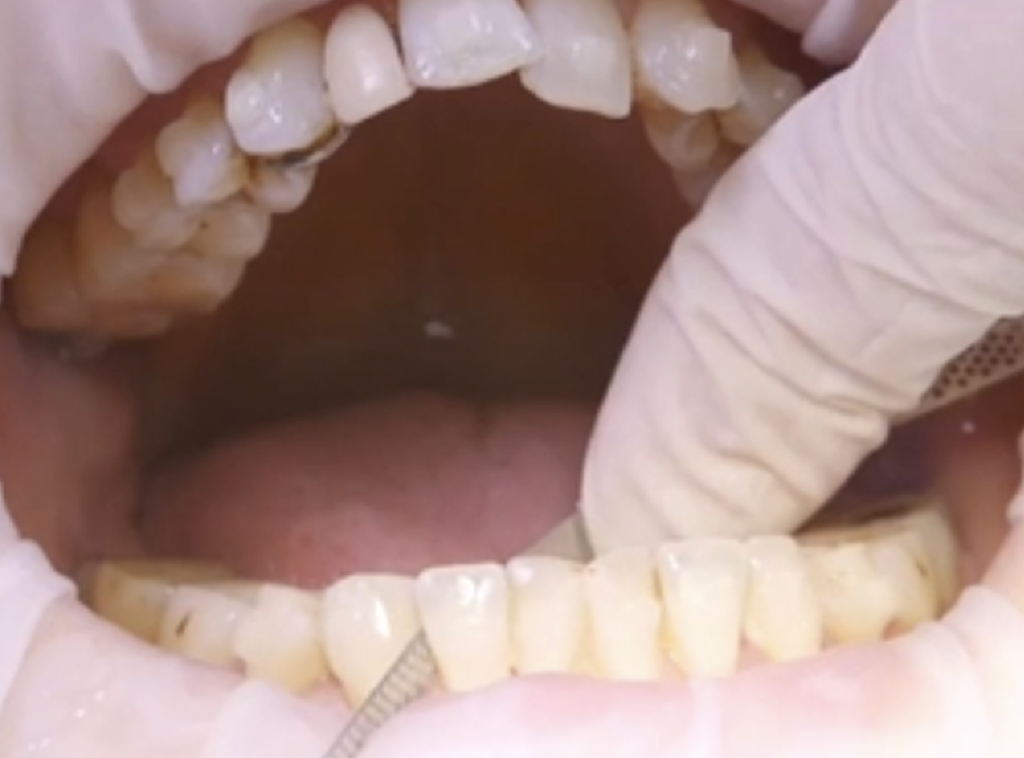

Interproximal reduction (IPR) involves removing small, precise amounts of enamel between selected teeth, typically 0.2mm to 0.5mm per contact, to create space for alignment and improve tooth proportions. When properly performed, it is a safe, effective, and conservative approach to managing mild to moderate crowding, enhancing aesthetics, and promoting long-term stability.

- IPR doesn’t need to span the full height of the tooth; it targets specific areas to maintain natural tooth shape. Barrel-shaped incisors may require more apically placed IPR for a natural finish

- IPR of maximum 0.3mm per contact in the anterior region and up to 0.5 mm in the posterior region is often sufficient for space creation and alignment.